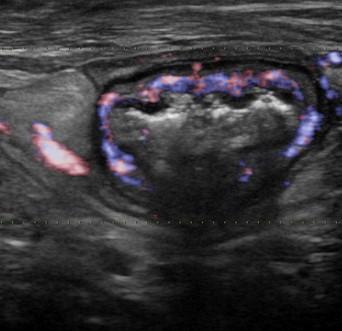

Viêm ruột

» Thông tin: Nữ giới – 55 tuổi.

» Lâm sàng: Tiêu chảy.